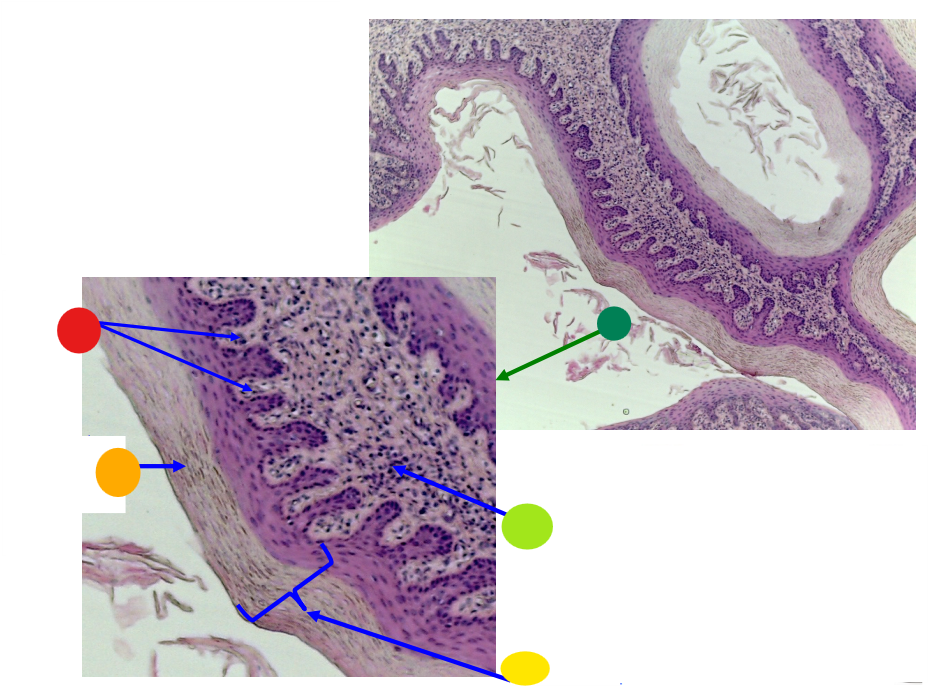

red

tunica albuginea

orange

primordial follicles

yellow

follicular cells

light green

primary oocyte

dark green

granulosa cells

light blue

primary follicles

what is this?

ovary

red

primordial follicles

red

primary follicles

red

tunica albuginea

orange

primary oocyte

yellow

primordial follicles

red

granulosa cells

orange

primary oocyte

what is this

primary follicle

red

tunica albuginea

orange

primordial follicles

red

primary follicle

orange

secondary follicles

what is this

tertiary follicle